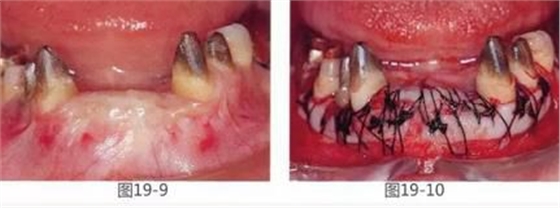

圖19-9 GBR后1年2個月的狀態(tài)。這時橋冠基牙周圍幾乎沒有附著齦,齦緣呈現(xiàn)出炎癥。

圖19-10 為了獲得基牙周圍的附著齦,在頰側(cè)以及舌側(cè)進(jìn)行FGG(游離齦移植)。